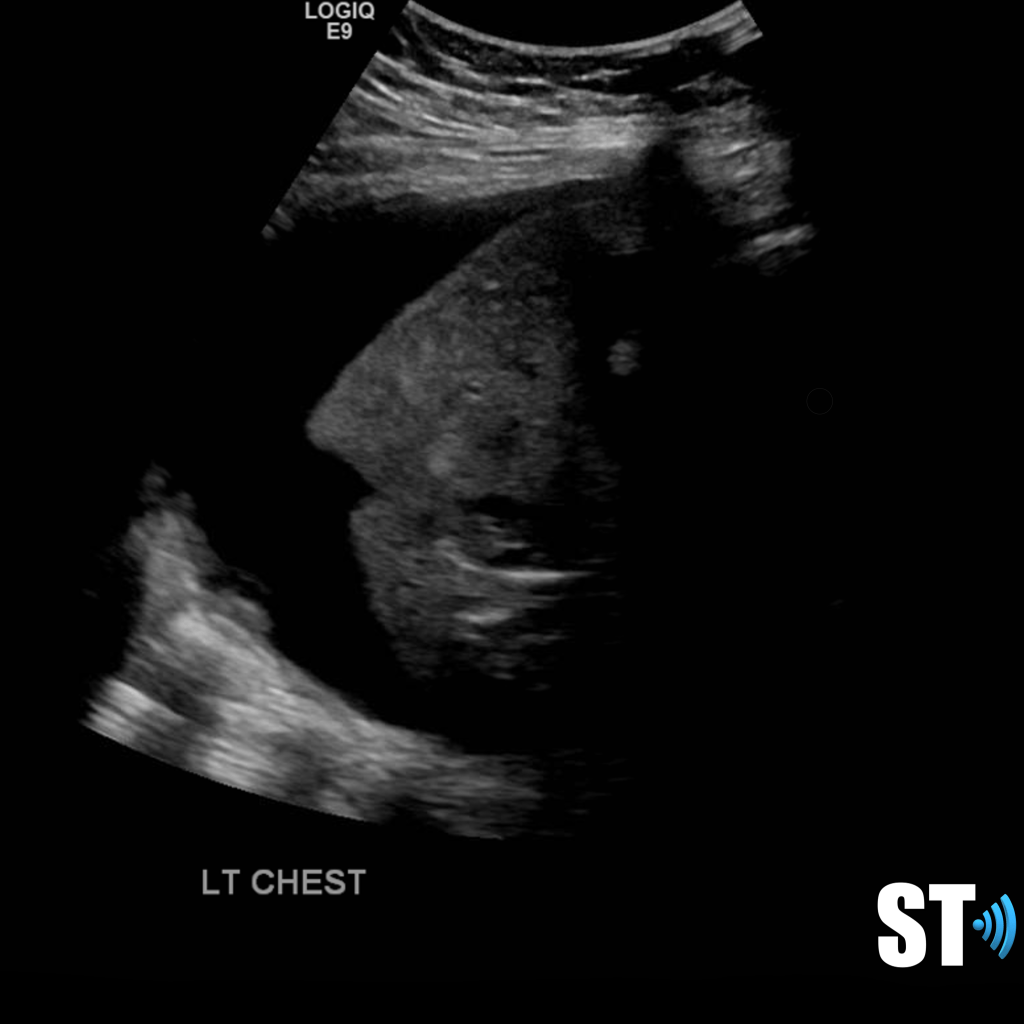

Another study on ultrasound findings found these types of lesions:

- rough discontinuous pleural line

- subplueral consolidation

- visible b-lines

- pleural effusion

- poor blood flow on consolidated lung tissue with color doppler

Potential ultrasound findings: (note these are non Covid-19 patients)

Pleural Effusion